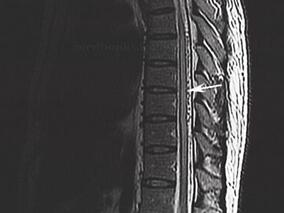

1小时条评论【病例资料】 患者,男性,34岁。因双下肢麻木无力、跛行半年,二便困难3个月于2013年2月16日入院。 现病史:患者于半年前无明显诱因出现双下肢无力,以右下肢为著,伴双膝以下发凉、麻木感,不伴有下肢肿胀、关节畸形,上述症状逐渐加重,出现右下肢行走困难,伴...